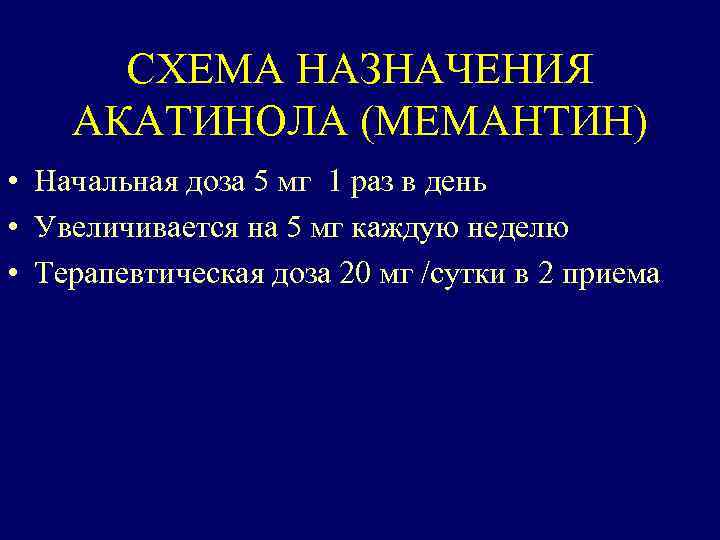

СХЕМА НАЗНАЧЕНИЯ АКАТИНОЛА (МЕМАНТИН) • Начальная доза 5 мг 1 раз в день • Увеличивается на 5 мг каждую неделю • Терапевтическая доза 20 мг /сутки в 2 приема